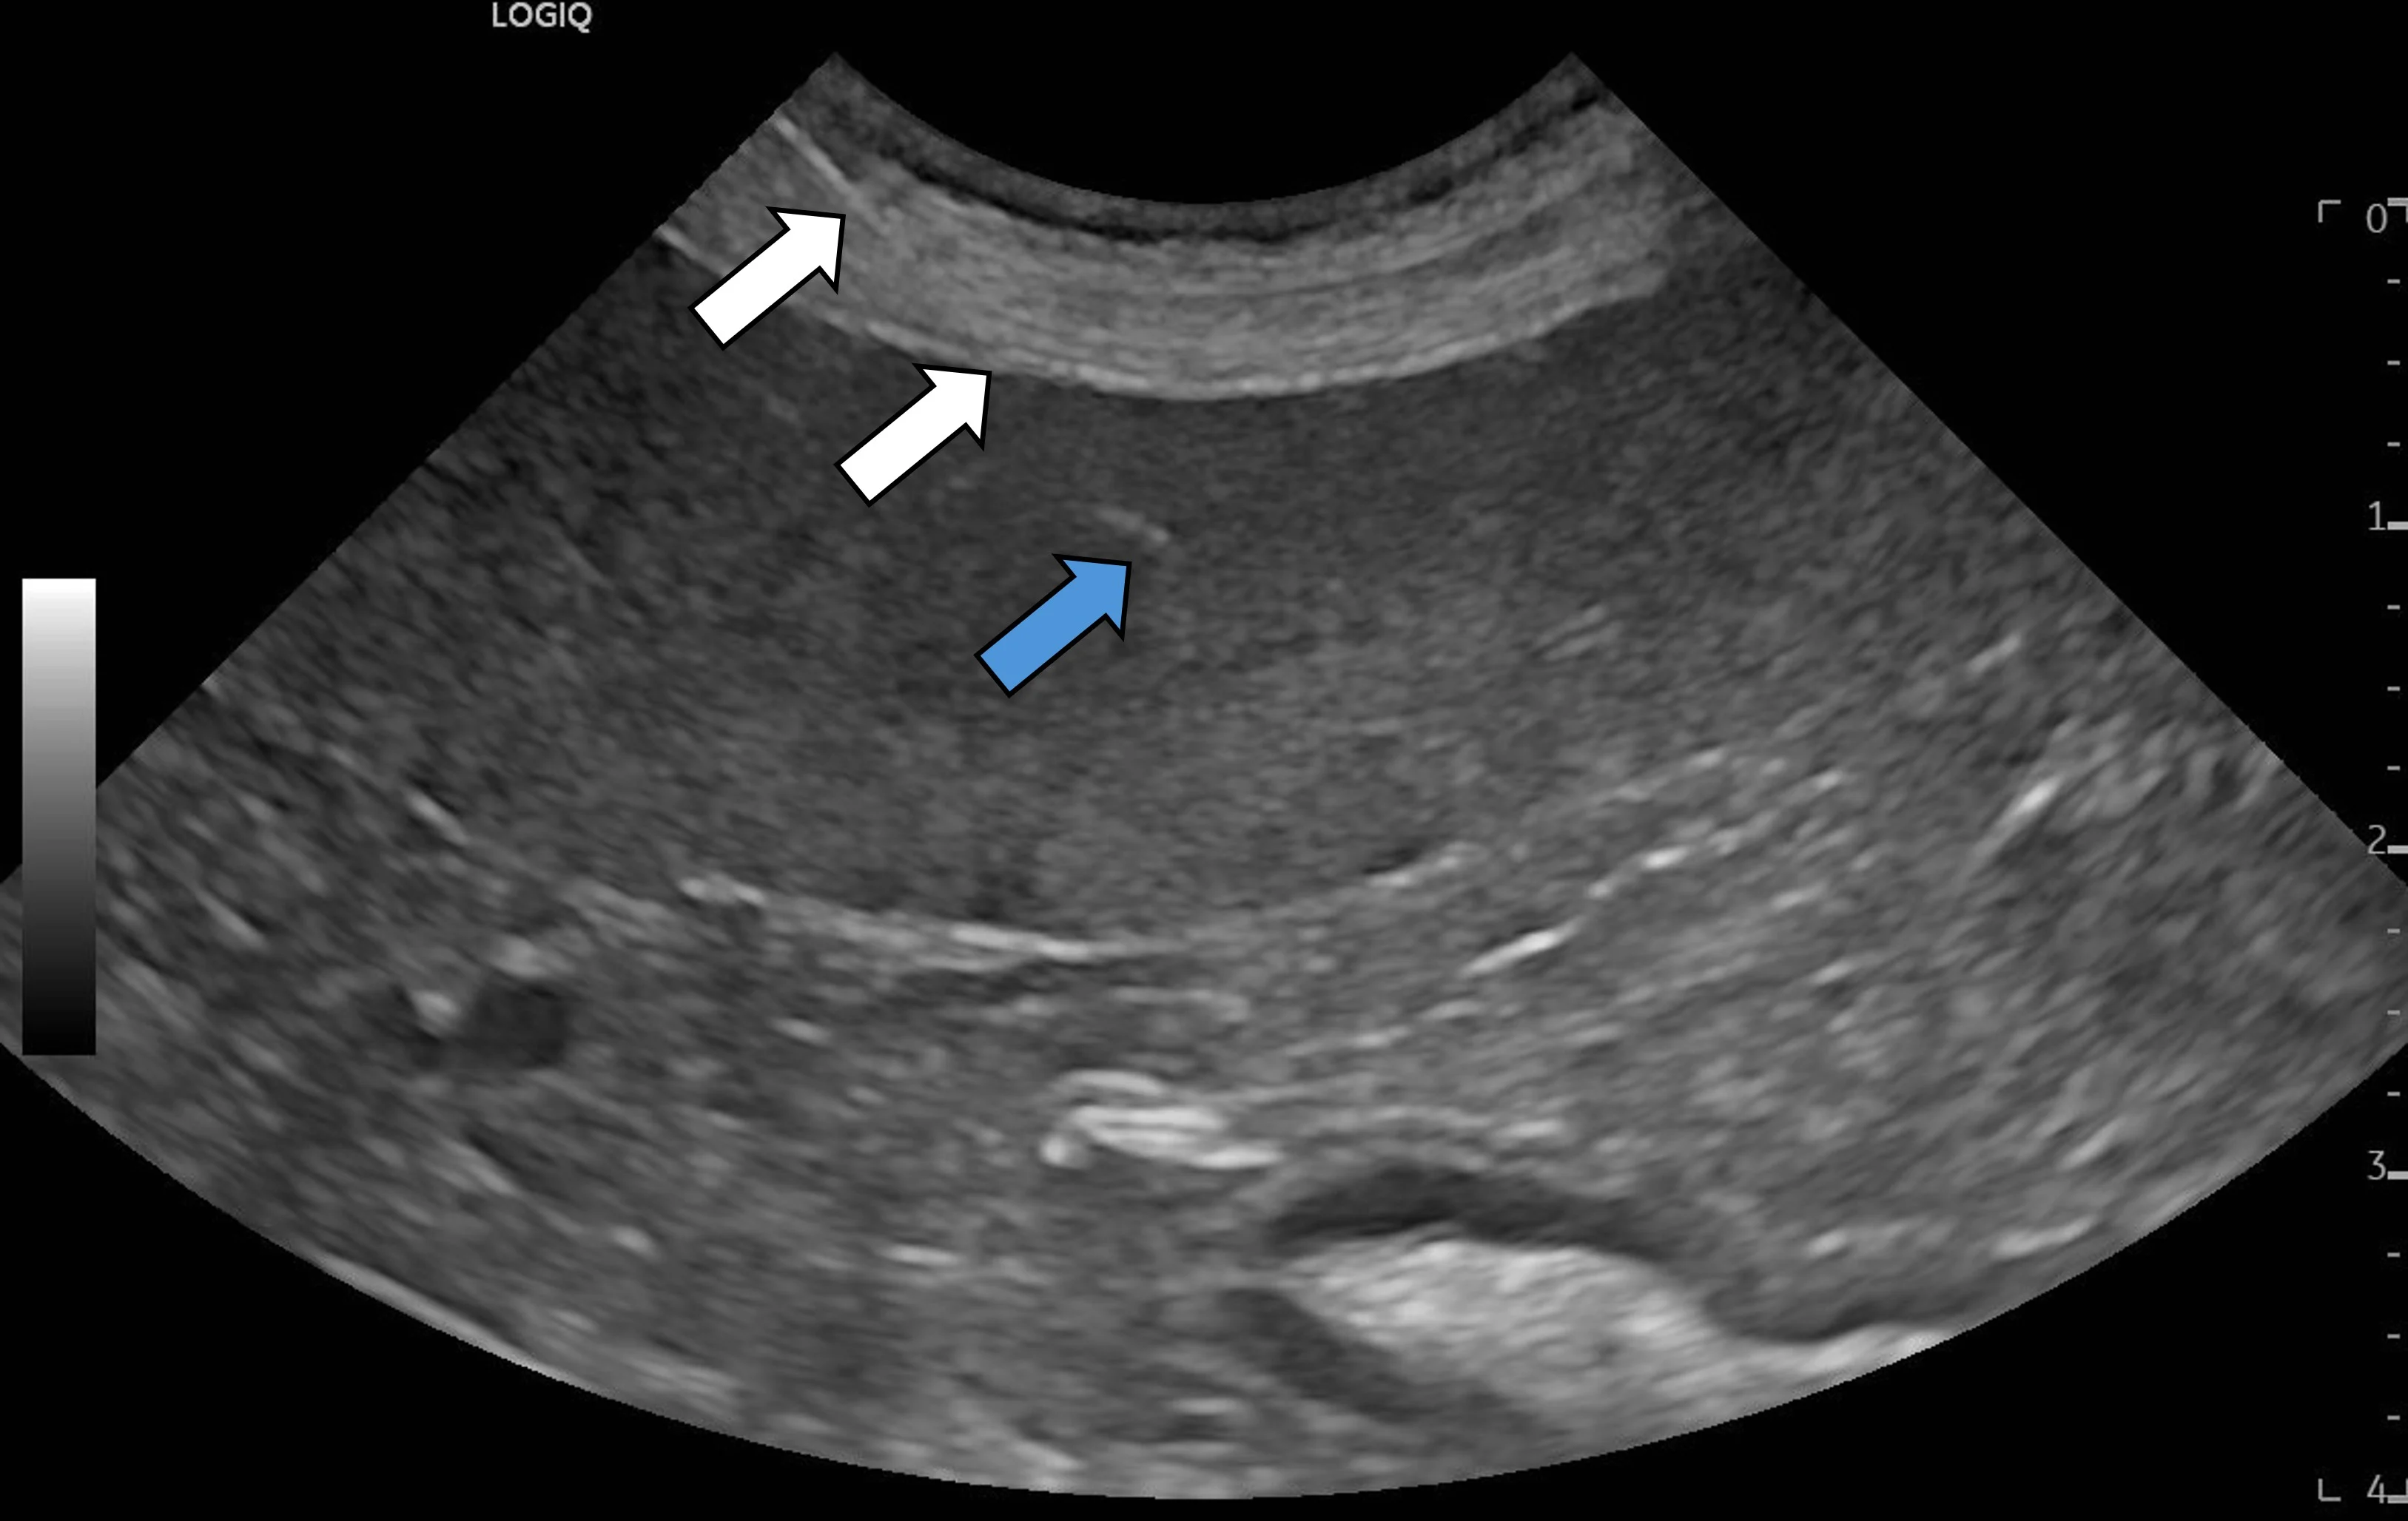

Step 7: Insert the Needle & Collect a Sample From the Target Lesion or Organ

Ensuring the needle is in the same plane as the beam of sound, insert the needle through the skin immediately next to the transducer and a short distance into the superficial soft tissues. Identify the needle on the ultrasound machine screen as a thin, hyperechoic linear structure. Make small adjustments to the needle or transducer so the entire needle (white arrows), including the tip (blue arrow), is completely visible.